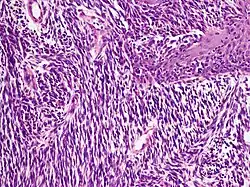

Noduläres Melanom

Aufgrund seines frühen vertikalen Wachstums erreicht diese Form des Melanoms schnell eine große Tiefenausdehnung. Seine Entstehung aus einem gutartigen melanozytären Nävus gilt als selten, eher wird vom nodulären Melanom als gemeinsamer Endzustand zunächst oberflächlich wachsender Melanome mit kurzer horizontaler Wachstumsphase ausgegangen.

Entsprechend seiner nodulären (knotigen) Konfiguration zeigt sich histologisch ein halbkugelig vorgewölbter, oft asymmetrisch angelegter Tumor, der durch eine abgeflachte, häufig auch ulzerierte Epidermis überkleidet wird. Ist die Epidermis erhalten, weist sie in der Regel eine epidermale Melanomkomponente auf, die die dermale Komponente seitlich je nach Lehrmeinung nicht oder maximal über drei angrenzende Retezapfen überragt.

Die dermale Komponente besteht aus einem soliden knotigen Verband oder kleinen Nestern atypischer Melanozyten mit verdrängendem Wachstum zur Tiefe. Die Zellen sind zumeist groß und rundlich, aber auch Spindelzellen, kleine nävusartige Zellen und mehrkernige Riesenzellen kommen vor. Obwohl die Tumorzellen bei geringer Vergrößerung relativ gleichförmig wirken können, zeigen sich bei hoher Vergrößerung in Größe, Form und Chromatingehalt (Chromatin: genetisches Grundmaterial des Zellkerns) variable Zellkerne mit deutlich sichtbaren Nukleolen. Mitosen finden sich auch in tiefen Anteilen der dermalen Komponente. Der Zytoplasmagehalt der Melanozyten ist im Verhältnis zur Kerngröße niedrig und das Zytoplasma enthält unterschiedlich große oder auch als puderstaubartig bezeichnete Melaningranula. Eine Ausreifung der Melanozyten zur Tiefe fehlt.

In der angrenzenden Dermis bestehen ein mehr oder weniger dichtes Infiltrat aus Lymphozyten und Melanophagen, Fibroplasie (Bildung faserigen Bindegewebes) und erweiterte Blutgefäße.[45]